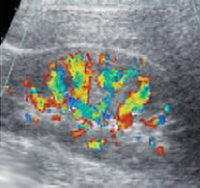

При проведении пробы Зимницкого выявляется изогипостенурия. УЗИ почек свидетельствует о снижении толщины паренхимы и уменьшении размера почек. Снижение внутриорганного и магистрального почечного кровотока выявляется на УЗДГ сосудов почек. Рентгенконтрастную урографию следует применять с осторожностью из-за нефротоксичности многих контрастных препаратов. Перечень других диагностических процедур определяется характером патологии, ставшей причиной развития ХПН.

- УЗИ почек (позволяет выяснить, как развивался отказ почек, а также вероятные причины состояния);